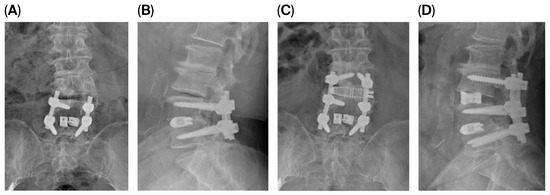

Comprehensive radiological evaluation was performed using standing anteroposterior and lateral radiographs obtained preoperatively and at 3 and 12 months postoperatively and at the final follow-up. We measured lumbar lordosis (LL) as the Cobb angle from L1 to S1 and segmental lordosis (SL) as the Cobb angle at the operated level. Pelvic tilt (PT) was recorded. Sagittal vertical axis (SVA) was measured as the horizontal distance from the C7 plumb line to the posterosuperior corner of S1. Disk height (DH) was measured at both anterior and posterior margins of the vertebral endplates (Figure 1). Solid fusion was defined as continuous bridging bone across the disk space with less than 3 degrees of angular motion on dynamic flexion–extension radiographs [12,13].

Figure 1. Measurement of anterior disk height (ADH) and posterior disk height (PDH) on lateral radiographs.

ADH was measured as the vertical distance between the anterior margins of the superior and inferior vertebral endplates at the operated level. PDH was measured as the corresponding vertical distance between the posterior endplate margins.

3.5. Illustrative Case

We present the case of an 80-year-old female who developed symptomatic cranial adjacent segment degeneration at L3–4 following posterior lumbar interbody fusion at L4–5, performed 4 years ago. Her primary complaint was progressive right anterior thigh pain. Preoperative pain assessment revealed VAS scores of 8 for back pain and 7 for leg pain. Standing radiographs showed decreased disk height at L3–4 with maintained alignment at the previously fused L4–5 segment. MRI demonstrated severe disk degeneration at L3–4 with central canal and bilateral foraminal stenosis.

The patient underwent PSP-LLIF at L3–4 with supplemental posterior instrumentation extending from L3 to L5, incorporating the L3–4 level into the existing fusion construct. The entire procedure was completed in 110 min without position change. Intraoperative fluoroscopy confirmed appropriate cage positioning. At 12-month follow-up, VAS scores improved to 3 for back pain and 2 for leg pain. Radiological measurements showed LL increased from 27.87 degrees to 36.94 degrees, SL increased from 6.16 degrees to 15.99 degrees, ADH increased from 7.03 mm to 12.87 mm, and PDH increased from 5.85 to 9.39 (Figure 2). Dynamic radiographs confirmed solid fusion without evidence of hardware loosening, cage subsidence, or migration.

Figure 2. Anteroposterior (AP) and lateral radiographs before and after surgery in a representative case of prone single-position lateral lumbar interbody fusion (PSP-LLIF). (A,B) Preoperative and (C,D) 12-month postoperative AP and lateral standing radiographs of an 80-year-old female following PSP-LLIF at L3–4 with supplemental posterior instrumentation from L3 to L5. Postoperative radiographs demonstrate restored L3–4 disk height, increased lumbar lordosis (LL) and segmental lordosis (SL), and improvement in anterior disk height (ADH) and posterior disk height (PDH), with confirmed fusion and no evidence of hardware loosening, cage subsidence, or migration at 12 months.